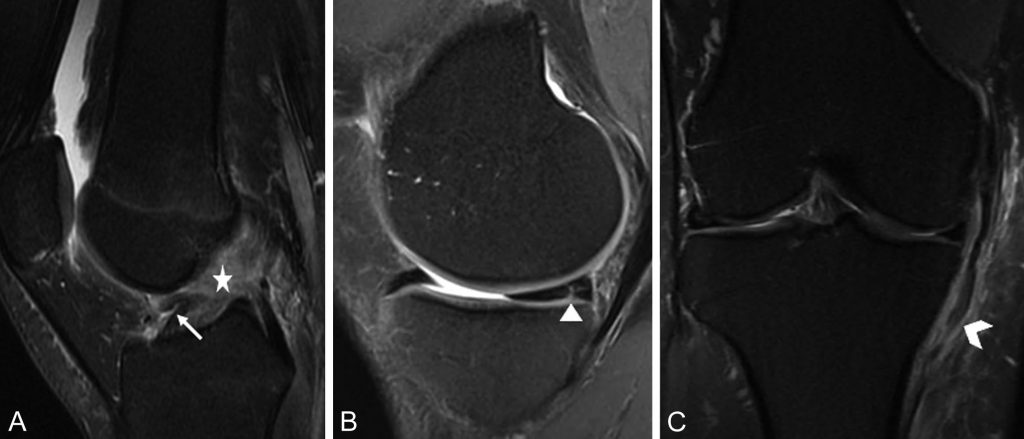

L’IRM est l’examen de référence pour l’exploration des lésions ménisco-ligamentaires du genou. L’IRM confirme la rupture du LCA et permet de faire l’inventaire des lésions ménisco-ligamentaires et ostéochondrales associées (figure 79.2).

Fig. 79.2 IRM en pondération DP Fat Sat.

L’IRM montre dans un plan sagittal : (A) une rupture en plein corps du LCA (flèche) avec une échancrure vide siège de remaniements œdémato-hémorragiques (étoile) ; (B) une lésion verticale de la corne postérieure du ménisque médial (tête de flèche) ; et, dans un plan coronal (C) : un aspect épaissi, distendu du ligament collatéral médial (tête de flèche) avec des remaniements œdémateux périligamentaire.

Source : CERF, CNEBMN, 2022.